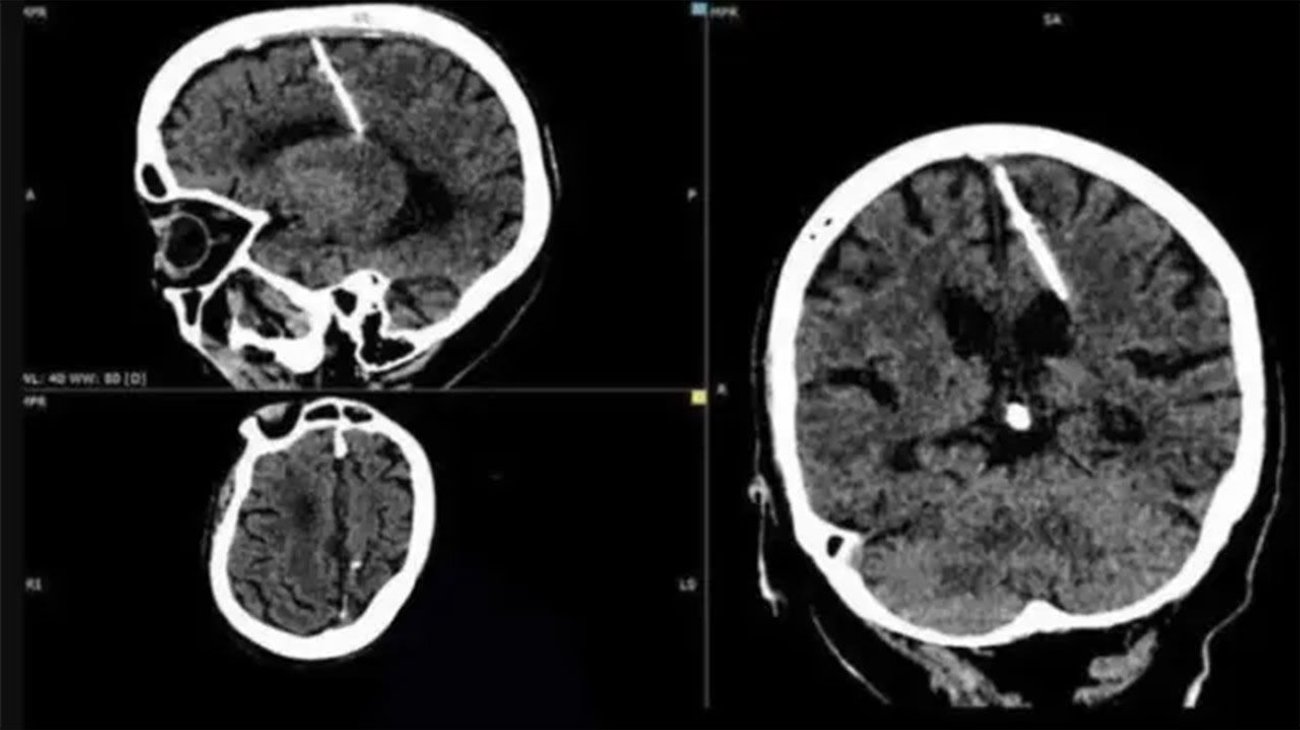

Una mujer de 80 años se sometió a una tomografía digital y los radiólogos le encontraron una aguja de 3 centímetros clavada en el cerebro.

La aguja fue encontrada en el lóbulo parietal izquierdo del cerebro de la mujer.